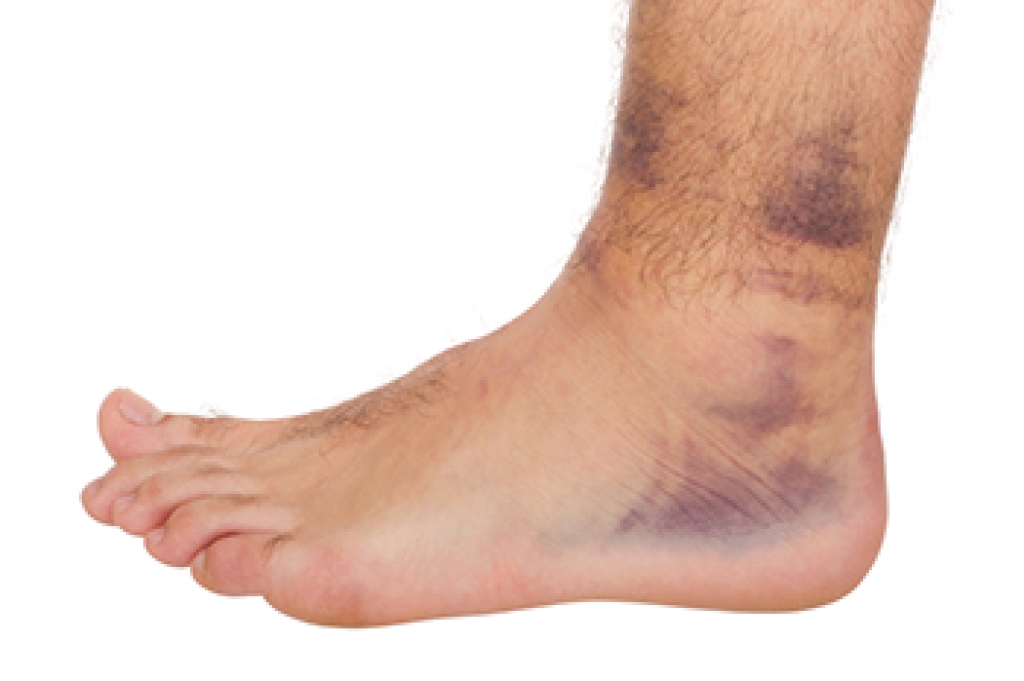

Pain from the fractures occur in the area of the fractures and can be constant or intermittent. It will often cause sharp or dull pain with swelling and tenderness. Engaging in any kind of activity which involves high impact will aggravate pain.